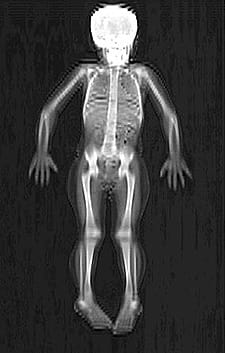

The Schubert Research Clinic (SRC) Body Composition Core Lab provides researchers two imaging techniques to assess bone mass, bone density and body composition of humans.

DXA imaging provides a two-dimensional measurement of:

• Total body bone mass

• Total body lean mass and fat mass

• Regional bone mass and density

The Body Composition Core uses Hologic densitometers (Hologic Inc., Bedford, MA) to perform DXA scans on both clinical and research patients.

Scans available include: whole body, AP lumbar spine, lateral spine, proximal femur or hip, forearm and distal femur.